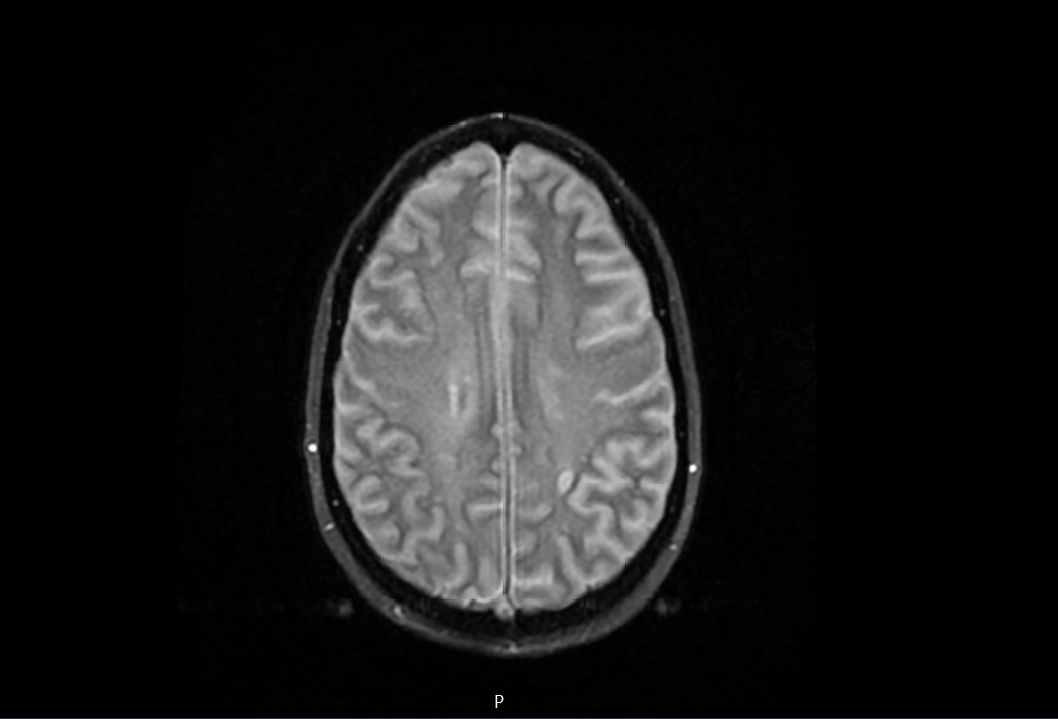

Case Presentation: 46-year-old female patient with a past medical history of ESRD on hemodialysis, DVT on chronic anticoagulation with apixaban, chronic HFrEF and history of injectable drug use (fentanyl) who presented with a chief complaints of progressive headache followed by rapidly progressive confusion requiring intubation for airway protection. Diagnostic lumbar puncture was considered however deferred given apixaban coagulopathy and thrombocytopenia. Empirical broad-spectrum antibiotic therapy along with acyclovir was initiated for suspicion of meningitis/encephalitis. CT head within 12 hours of presentation suggested evolving cerebral edema and CT angiogram of the head revealed diminished anterior intracranial circulation. Patient was treated with hypertonic saline. MRI of the brain revealed diffuse global cerebral and cerebellar diffusion restriction without diffuse enhancement (suggesting against an infectious etiology) likely consistent with opiate drug abuse. EEG ruled out nonconvulsive status epilepticus. Clinical course and presentation was highly suspicious for fentanyl induced leukoencephalopathy which can cause diffuse cerebral edema. Hospital course was complicated by hemodynamic instability requiring multiple vasopressor support and despite aggressive medical therapy, the patient continued to deteriorate clinically. Follow-up CT revealed catastrophic cerebral edema with complete effacement of all ventricles and sulci with evidence of transtentorial herniation. NM brain scan SPECT demonstrated an absence of cerebral perfusion. Serial brain death examinations demonstrated absence of all brainstem reflexes and cortical function without any confounding conditions and brain death was eventually declared.

Discussion: Opiate induced toxic leukoencephalopathy (TLE) is a rare and life-threatening complication of fentanyl overdose which is frequently under-recognized. Pathophysiology involves damage of brain white matter with myelin sheath injury. Clinical manifestations range from mild confusion to stupor, coma, and death. Prognosis depends upon the degree of damage. Differentials including hypoxic, ischemic, vascular, metabolic and infectious causes should be ruled out by comprehensive clinical evaluation, imaging, and lab testing (LP, EEG). Management is usually supportive, focusing on controlling intracranial pressure to avoid neurological complications with limited role of hyperosmolar therapies and corticosteroids. Severe cases may require intubation for airway protection and emergency neurosurgical intervention.